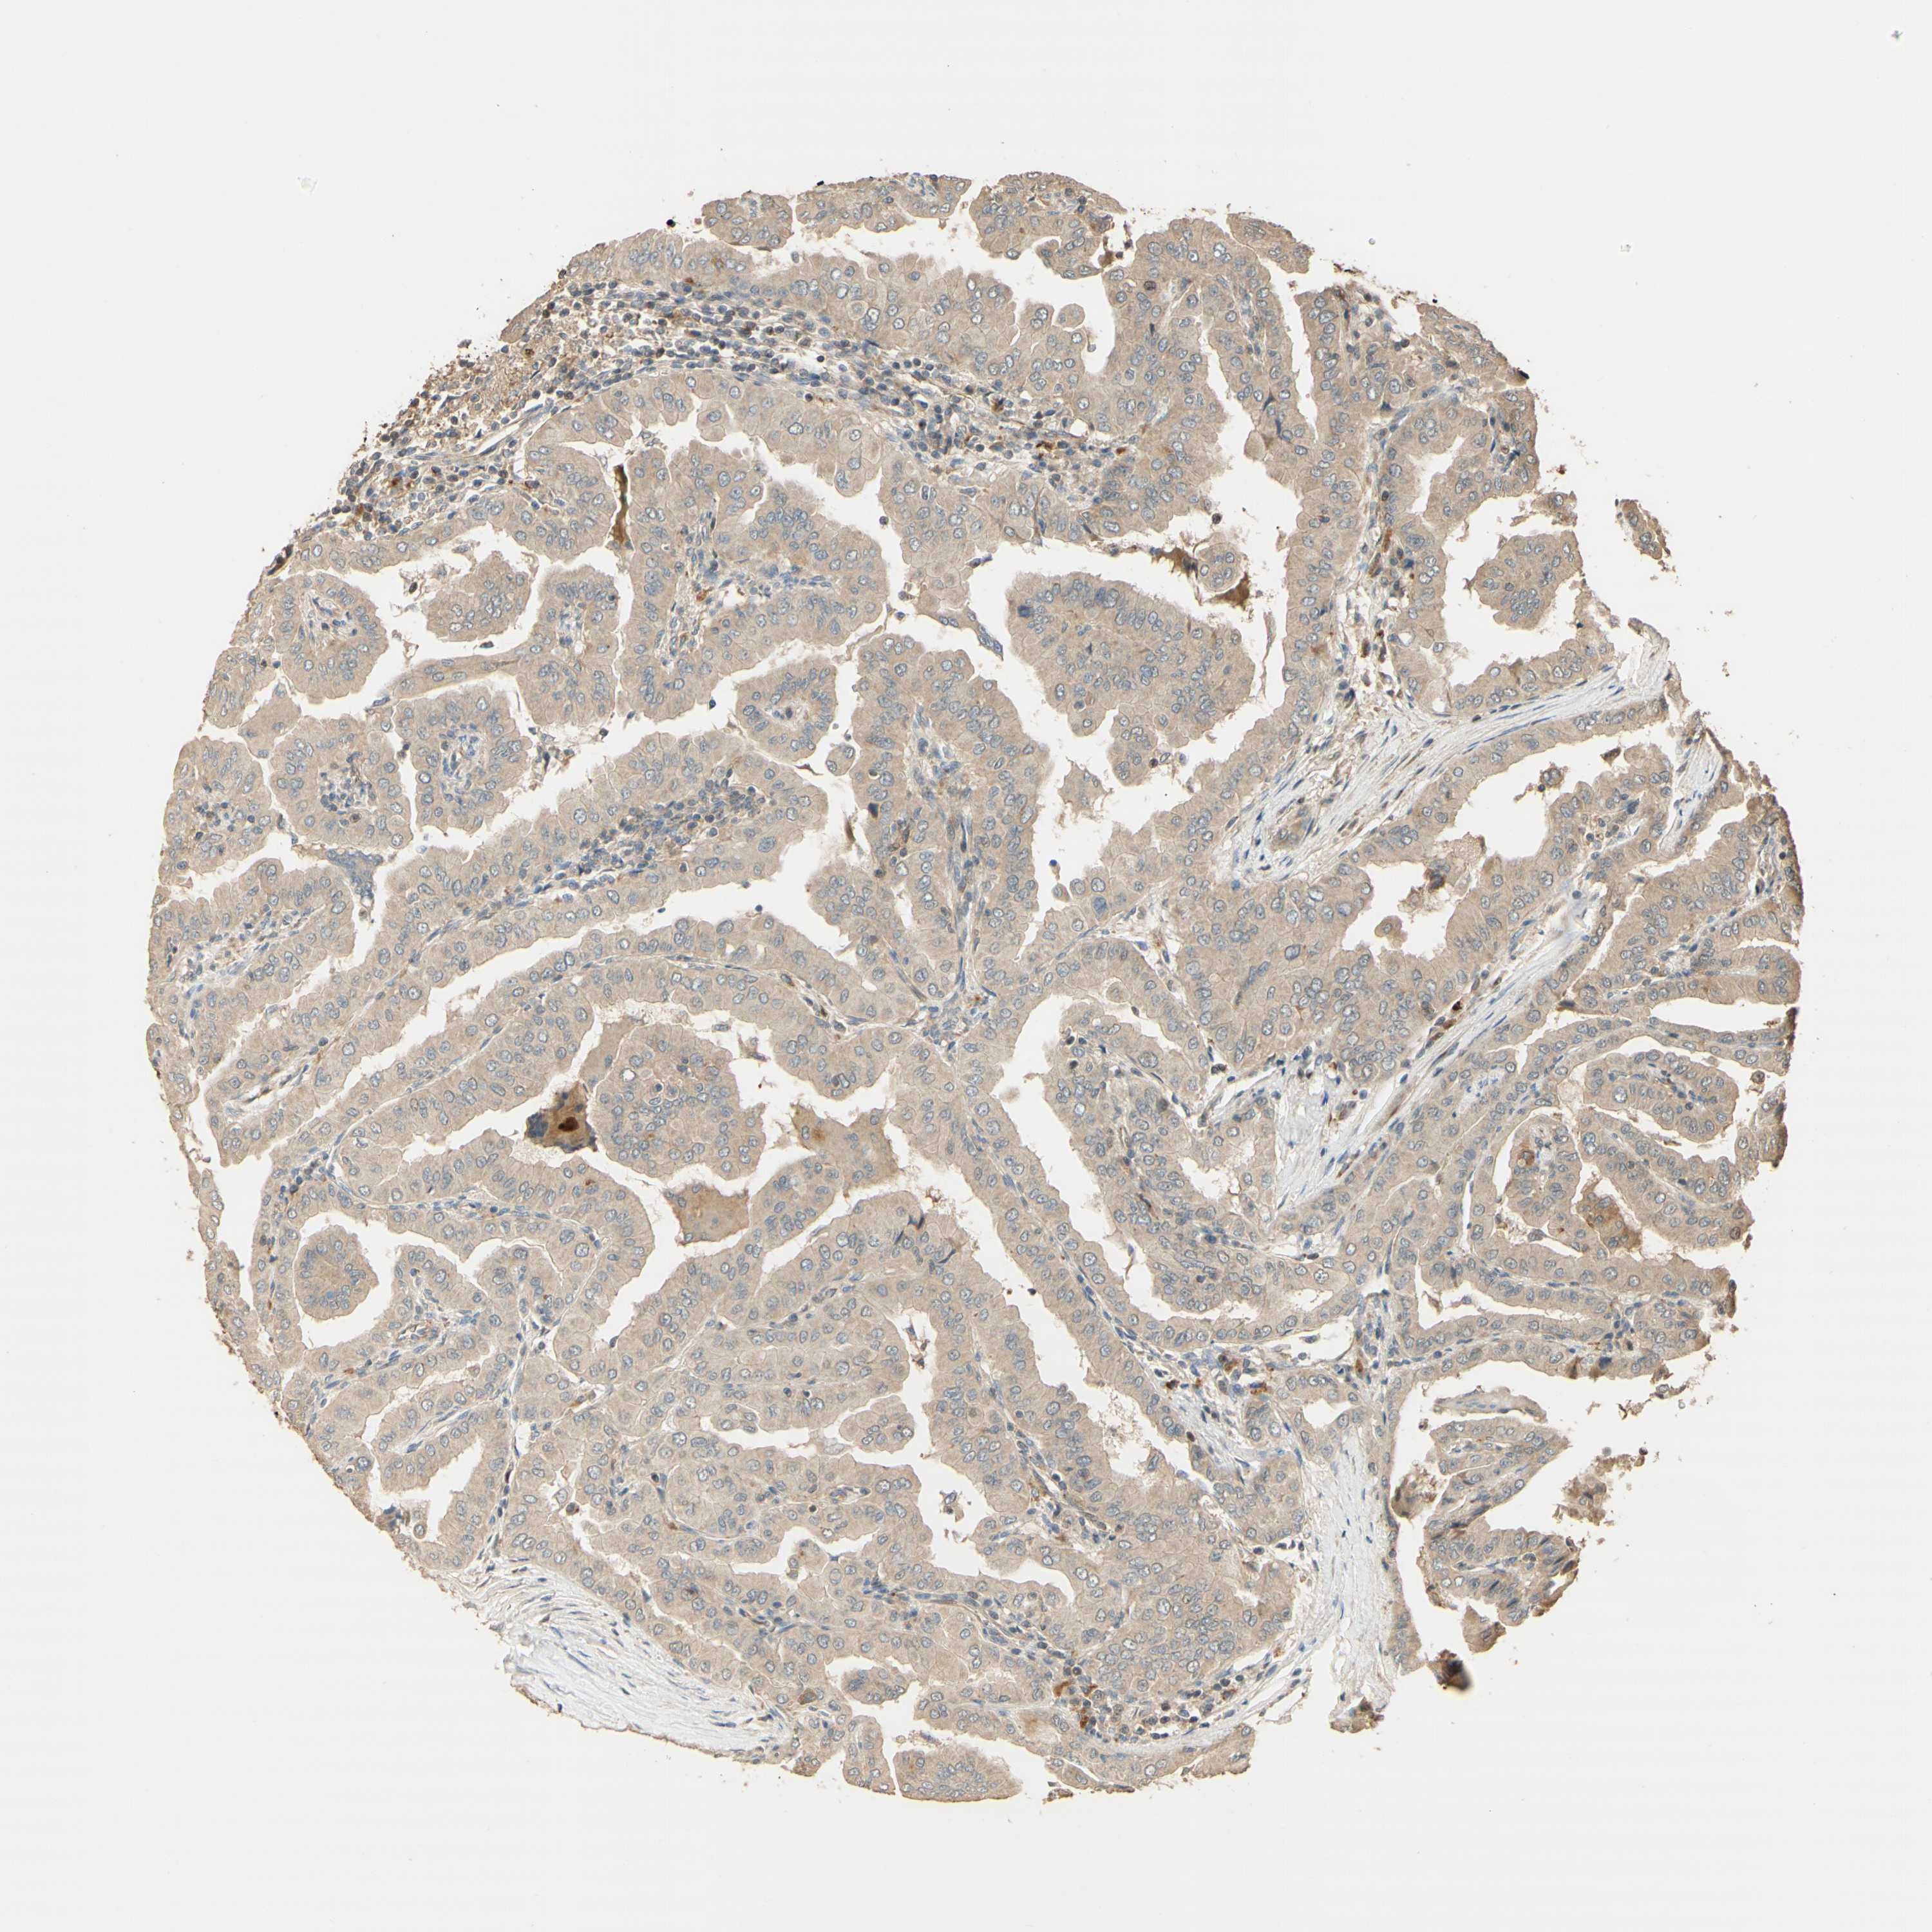

THYROID CANCER - Protein expressioni

A mouse-over function shows sample information and annotation data. Click on an image to view it in a full screen mode. Samples can be filtered based on level of antibody staining by selecting one or several of the following categories: high, medium, low and not detected. The assay and annotation is described here.

Note that samples used for immunohistochemistry by the Human Protein Atlas do not correspond to samples in the TCGA dataset.

Antibody stainingi

Antibody staining in the annotated cell types in the current human tissue is reported as not detected, low, medium, or high, based on conventional immunohistochemistry profiling in selected tissues. This score is based on the combination of the staining intensity and fraction of stained cells.

Each image is clickable and will lead to virtual microscopy that enables deeper exploration of all samples and also displays staining intensity scores, fraction scores and subcellular localization as well as patient and tissue information for each sample.

Antibody HPA069474

Antibody CAB011682

Staining

High

Medium

Low

Not detected

Intensity

Strong

Moderate

Weak

Negative

Quantity

>75%

75%-25%

<25%

None

Location

Nuclear

Cytoplasmic/membranous

Cytoplasmic/membranous,nuclear

Papillary adenocarcinoma, NOS

Follicular adenoma carcinoma, NOS